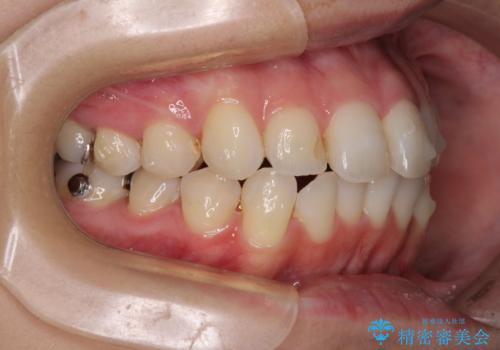

【モニター】前歯のデコボコをインビザラインできれいに整える

- 前歯のデコボコを気にして来院された患者様です。

主に下顎歯列全体の後方移動とIPR(歯と歯の間を削る)によってデコボコが解消するように設計し、インビザラインにより治療を行うこととしました。

舌突出癖がある方ですと、叢生が解消すると同時に前方に拡大されてしまいますが、ゴムかけをしっかりと行ってくださったこともあり、スッキリとした仕上がりとなりました。